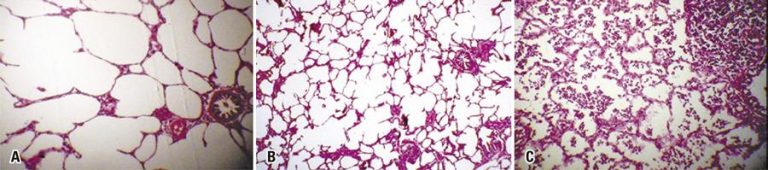

RESUMO Objetivo Avaliar a exequibilidade e a aplicação de um sistema de baixo custo de crioterapia. Métodos Estudo experimental realizado com um suíno da raça Landrace, 25kg, submetido à cervicotoracolaparotomia longitudinal, com exposição de traqueia, tórax e abdome. Procedemos ao congelamento das estruturas em tempos diferentes (5, 10 e 15 segundos) com jato contínuo. A crioterapia foi realizada com gás fluoretado (tetrafluoretano), na forma de spray em tubo, que atinge a temperatura de -47°C (DermaFreeze®, Emdutos; registro ANVISA 80409950001; preço […]